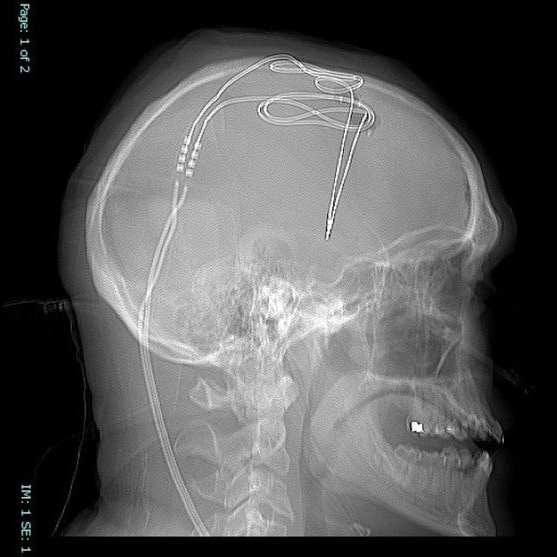

Operację przeprowadzono 1 listopada i trwała niemal siedem godzin. Pacjent w tym czasie pozostawał przytomny, by móc opowiadać na pytania operujących lekarzy. Na podobny implant czeka trzy kolejne osoby. W trakcie operacji do jądra półleżącego, dokładnie tam, gdzie znajduje się układ nagrody, wprowadzone zostały elektrody. Stymulator składa się z baterii połączonej przewodem z elektrodami umieszczonymi w mózgu. Przewód łączący znajduje się pod skórą na szyi, a generator impulsów, czyli bateria, umocowana jest w okolicy obojczyka lub klatki piersiowej. Stymulator jest najpierw ustawiany przez lekarza, który może zmieniać jego parametry, by dostosować go do aktywności mózgu. W późniejszym czasie aktywność mózgu będzie monitorowana zdalnie.